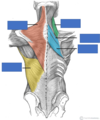

Red

Biceps brachii

Innervation: Musculocutaneous nerve C5-C7

Action: Supination of the forearm and flexion of arm at elbow and shoulder

Blue

Brachialis

Innervation: Musculocutaneous nerve (little radial)

Action: Flexor of the arm at elbow

Green

Coracobrachialis

Innervation: Musculocutaneous nerve

Action: Flexor of the arm at shoulder Supination of the arm

Triceps Brachii

Innervation: Radial nerve - C6-8 (mainly C7)

Action: Extension of the arm at the elbow